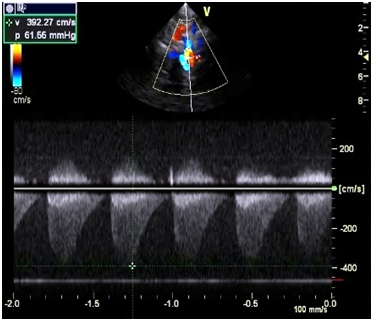

Investigations revealed hemoglobin value of 9g/dL, WBC count 4,000/cumm and platelet count was normal. Liver function test and renal function tests were normal. ECG showed the left ventricular hypertrophy. On chest X-ray there was a normal cardiac silhoutte and a normal lung parenchyma. Transthoracic echocardiography showed parachute-like mitral valve with a severe mitral stenosis (mitral valve size: 0.6 cm2, pressure gradient (Pg: 20 mmHg) causing obstruction to flow Figure 1. Aortic valve was bicuspid with a mild to moderate aortic stenosis (Pg: 40 mm Hg) Figure 2. Severe post-ductal coarctation of aorta with a diastolic tailing was seen on suprasternal view Figure 3. There was a Tiny mid muscular ventricular septal defect with left to right shunt. Small size patent ductus arteriosus with bidirectional shunt mainly left to right was present. Severe tricuspid regurgitation secondary to severe pulmonary hypertension (Right Ventricular systolic pressure = 84mmHg). Pulmonary artery was grossly dilated. There was mild left ventricular hypertrophy with a normal global systolic function and a normal ejection fraction. CT angiography revealed post ductal coarctation of aorta with patent ductus arteriosus with enlarged pulmonary trunk.

Figure 1B Continuous wave doppler studies demonstrated increased peak early (e) and late atrial (a) diastolic flow velocities, peak e-wave velocity is increased, 2.3 m/s.